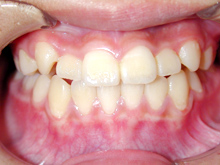

常滑市小林町在住 S.T様(15歳女性)

S.T様は下顎前歯の叢生が主訴でお母様と無料矯正相談で来院されました。

口を閉じる際に口元の緊張があり、横顔に突出感がありました。

以前に上顎前歯の部分矯正をされたご経験があるとお話しされておりました。

そのためか上顎犬歯の横幅(幅径)が通常より少なく思いました。

試料採取より診断の結果、上顎の前歯にも軽度の叢生があり、口元の緊張を改善し、

前歯の叢生の治療のために抜歯が必要であることを説明し、了承が得られたので本格矯正で治療をすすめることとなりました。

上顎前歯に軽度の叢生、下顎前歯に叢生がみられます前歯の上下の接触状態が緊密でなく軽度の舌癖の存在を疑います。

臼歯部は1歯 対 2歯で咬んでいます。

各ステージで順調に治療がすすみました。

治療は順調に進みました。

犬歯の幅径が狭い事の対応として犬歯にダイレクトボンディングを行う、

下顎前歯のストリッピングを行うなどのプランを考えましたがその両方とも行うことなく動的治療を完了しました。

舌癖の存在は後戻りの大きな原因となりますので今後の保定治療でも注意が必要で、引き続き舌癖の改善を行います。

治療期間:2年3ヶ月

治療費用:60万円